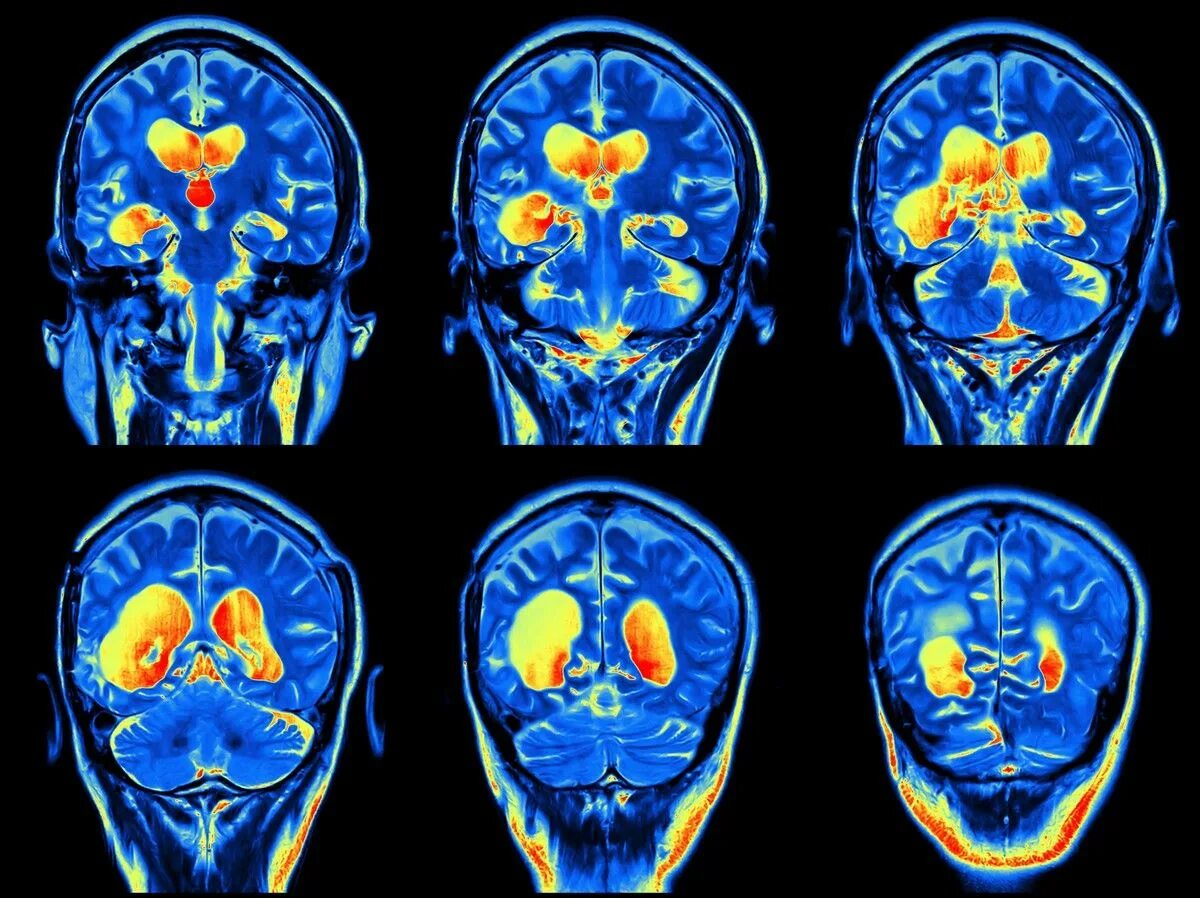

Мрт с контрастированием головного